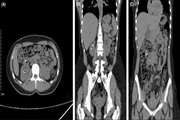

Benign hepatic schwannoma in a patient with chronic hepatitis B infection: A case report 1403/12/26 - 13:43